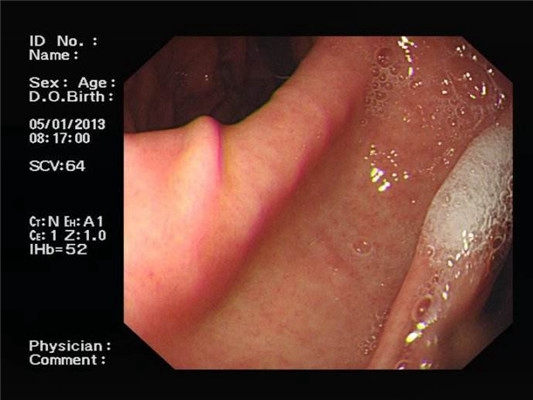

食道炎圖片